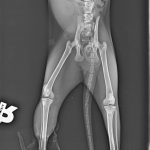

A sokktalanítás után, bódításban tudták csak megvizsgálni, borzasztóan félt és hatalmas fájdalmai voltak. Sajnos a fájdalom oka a hátsó lába iszonyatos sérülése volt. A térde szilánkosra törve és a lágy részek rendkívül súlyosan roncsolódtak. Az első orvosi vélemények szerint 75% az esélye, hogy ezt a lábat nem tudják megmenteni már, tegnap este azután az ortopéd orvos is megvizsgálta és az ő véleménye szerint sem menthető a lábikó. A mai nap stabilizálták az állapotát, erősítik kicsit és holnap sor kerül a műtétre. Az első lábacskája szintén zúzódott, nagyon be van dagadva, itt azonban megvan a remény a teljes gyógyulásra.